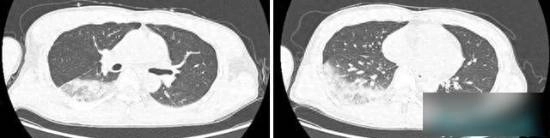

最终,家人送林师傅去医院检查,一系列检查结果出来后,所有人都大吃一惊:林师傅不仅双肺下叶有炎症,肝功能和肾功能也受到了损伤,多项炎症指标更是远远超出正常范围。

医生进一步询问病史后,了解到患者有“在口袋里养鹦鹉”的习惯,经过后续检查,最终确诊为鹦鹉热衣原体感染。